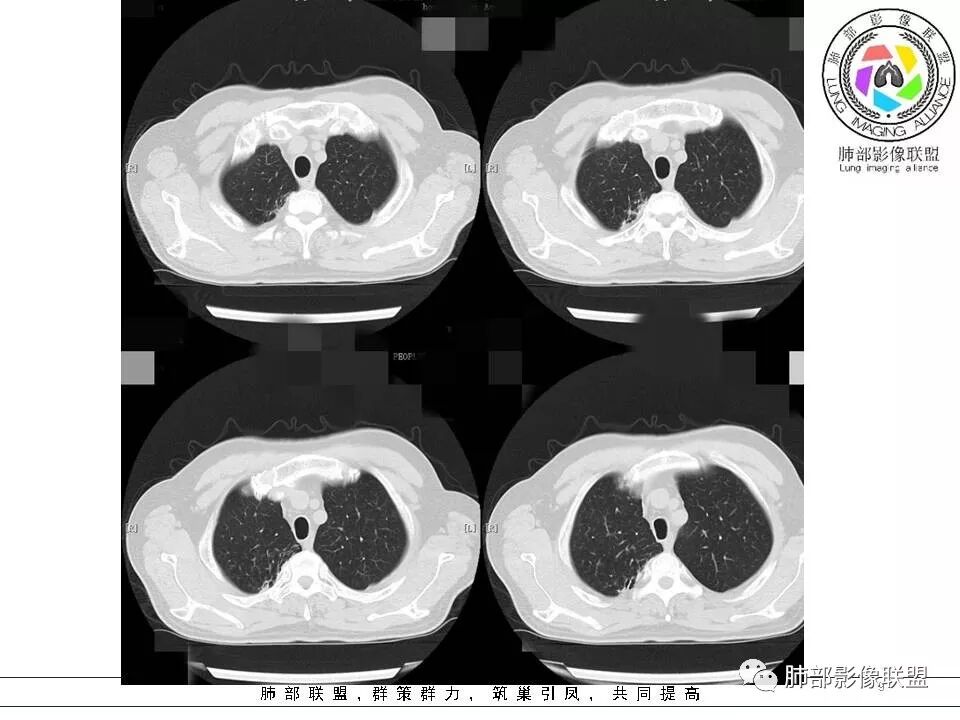

我们分析这2个病例的共同点:双肺都是以外周胸膜下分布为主,均表现为肺大片、斑片实变的肺炎性型改变,而且都有含气支气管的堵塞,这种残“支”败“叶”的异病同影的病例,那我们如何从影像上抽丝剥茧并结合临床分析病例呢?那我们现在按南边老师分析套路,从病变形态与分布、边缘的收缩性、病灶的走形方向、病灶的支气管变化、病灶内坏死及周围情况逐一分析;